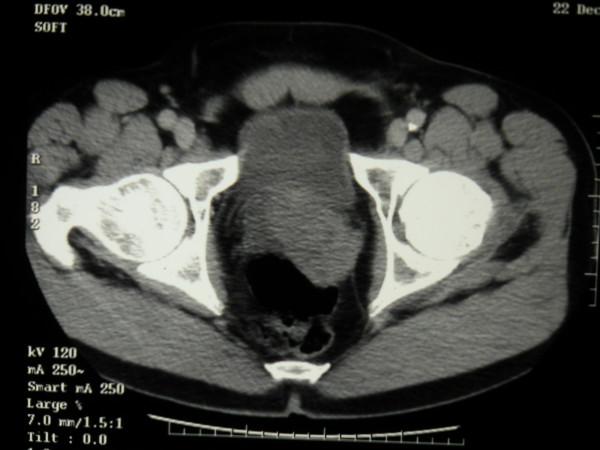

We present a case report of testicular seminoma in a 56 year old man with previously unreported histological findings. In this case seminoma tumour cells did not appear to have spread by the expected lymphatic route. There was no involvement of retro-peritoneal para-aortic lymph nodes. The tumour appeared to have spread directly along the vas deferans in the sub epithelial plane to the mesenteric lymph nodes.

我们报告一例56岁男性睾丸精原细胞瘤病例,具有此前未报道的组织学发现。在此病例中,精原细胞瘤肿瘤细胞似乎未按预期的淋巴途径扩散。腹膜后腹主动脉旁淋巴结未受累。肿瘤似乎是沿输精管在黏膜下层平面直接扩散至肠系膜淋巴结。

结论

这种类型的精原细胞瘤肿瘤扩散此前未被描述过,也不是精原细胞瘤公认的转移途径。在此病例中宏观临床表现为肿瘤标志物正常的I期肿瘤。然而,基于组织学和CT影像学检查结果,肿瘤的病理分期出人意料地升至III期。我们展示了这些不寻常的组织学发现。鉴于这一不寻常的组织学发现,我们强调准确分期以及在靠近腹股沟深环处切除精索的必要性。准确分期对于精原细胞瘤的治疗规划和随访至关重要,并决定预后。